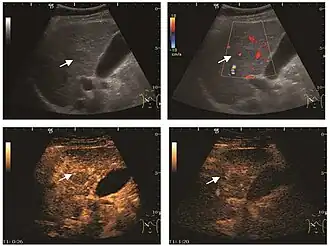

The ultrasound appearance is a well defined lesion, with very thin, almost unapparent walls, without circulatory signal at Doppler or CEUS investigation. The content is transonic suggesting fluid composition. The presence of membranes, abundant sediment or cysts inside is suggestive for parasitic, hydatid nature. Posterior from the lesion the acoustic enhancement phenomenon is seen, which strengthens the suspicion of fluid mass. They typically displace normal liver vessels but no vascular or biliary invasion occurs.

Hydatid liver cyst. Diagnostic criteria are the presence of membranes and sediment inside.

It is the most common liver tumor with a prevalence of 0.4 – 7.4%. It is generally asymptomatic but also can be associated with pain complaints or cytopenia and/or anemia when it is very bulky. It is unique or paucilocular. It can be associated with other types of benign liver tumors. Characteristic 2D ultrasound appearance is that of a very well defined lesion, with sizes of 2–3 cm or less, showing increased echogenity and, when located in contact with the diaphragm, a "mirror image" phenomenon can be seen. When palpating the liver with the transducer the hemangioma is compressible sending reverberations backwards. Doppler exploration reveals no circulatory signal due to very slow flow speed. CEUS investigation has real diagnosis value due to the typical behavior of progressive CA enhancement of the tumor from the periphery towards the center. The enhancement is slow, during several minutes, depending on the size of hemangioma and on the presence (or absence) of internal thrombosis. During late (sinusoidal) phase, if totally "filled" with CA, hemangioma appears isoechoic to the liver. Deviations from the above described behavior can occur in arterialized hemangiomas or those containing arterio-venous shunts. In these cases, differentiation from a malignant tumor is difficult and requires other imaging procedures, follow up and measurements of the tumor at short time intervals.[4]